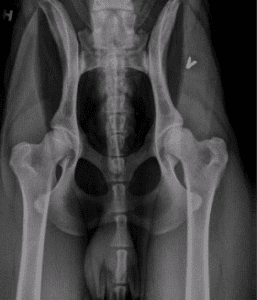

Overgangsvirvel "Lumbosacral transitional vertebrae, LTV"

Ved HD-avlesning har NKK sine avlesere de siste årene gitt opplysning om overgangsvirvel i nedre del av ryggen hvis dette påvises samtidig med screening for hofteleddsdysplasi (HD). Diagnosen blir vedlagt svarbrevet fra NKK. Overgangsvirvel er en medfødt misdannelse i en av ryggvirvlene. Misdannelsen kommer i overgangen mellom ryggsegmentene (nakke-bryst, bryst-lenderygg, eller lenderygg-korsbein), derav navnet overgangsvirvel. En overgangsvirvel ser ut som en blanding av to typer ryggvirvler. Noen ganger er overgangsvirvelen symmetrisk, andre ganger usymmetrisk og kan gi skjevheter i ryggen. En overgangsvirvel har som regel ingen klinisk betydning for hunden. I enkelte tilfeller kan imidlertid misdannelsen føre til at nervene nederst i ryggen kommer i klem, noe som vil gi symptomer som ryggsmerter eller halting.

NKK begynmte å loggføre hunder som får denne lidelsen juni 2019. Det er ikke alle HD-bilder som også vil kunne avlese for overgangsvirvel. Eksempelvis hvis hunden har avføring i tarmen, kan dette kamuflere forekomsten av overgangsvirvel, som kan føre til noe underrapportering av forekomsten. Til nå har det blitt avlest overgangsvirvel på 1438 engelske settere hvorav 28 har fått på det påvist. Det innebærer at 1,9 % av avleste hunder har fått påvist overgangsvirvel. På 101 hunder var det ikke mulig å lese av overgangsvirvel da hunden hadde avføring i tarmen, noe som utgjør 7% av hundene. En får ikke avleste alle hundene og det vil være en underrapportering av overgangsvirvel.